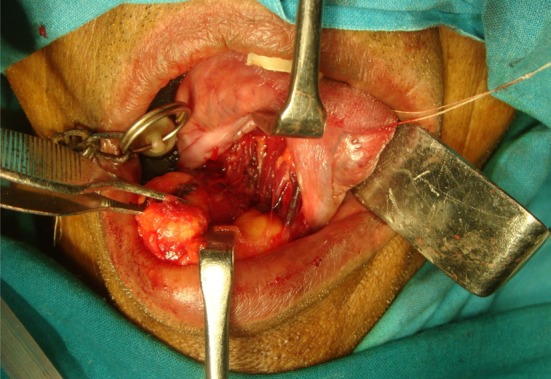

The surgical excision of the mass was done under general anesthesia. A midline, vertical mucosal incision was made directly over the crest of mass. The mucosa was dissected laterally to expose the superior aspect of the mass (Fig. 4). Extreme caution was taken and only blunt dissection was carried out throughout the procedure to prevent damage to the Wharton’s duct, lingual nerve, and sublingual gland. This yielded an unexpectedly soft, yellowish lobulated mass measuring 3.7 × 3.3 × 2.2 cm (Fig. 5). The classical sight of an adipose tissue coupled with a capsule surrounding its periphery reclassified our diagnosis as lipoma. The mass shelled out easily, with no adhesions to the surrounding structures. As the mass was in the submucosal plane, none of the vital structures in the floor of the mouth such as lingual nerve, sublingual gland and Wharton’s ducts were encountered during the dissection. After achieving good hemostasis the mucosal layer was closed together with absorbable sutures. Gross histopathological examination revealed round to oval matured fat cells (with peripherally placed nucleus) arranged in lobules separated by thin cords of fibers. Numerous striated muscles and few blood vessels containing lymphocytes and mast cells were evident. This was consistent with the diagnosis of a simple classical lipoma as shown (Fig. 6). Healing was uneventful. No recurrence was observed at 1 year follow-up.

Fig. 4.

Intra-operative appearance of the yellowish lobulated mass